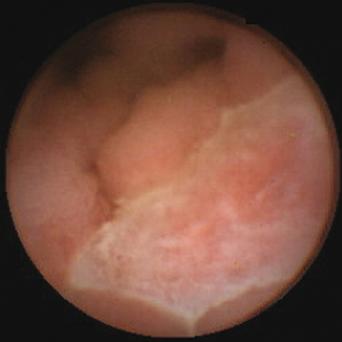

L’image

du jour

Illustration.